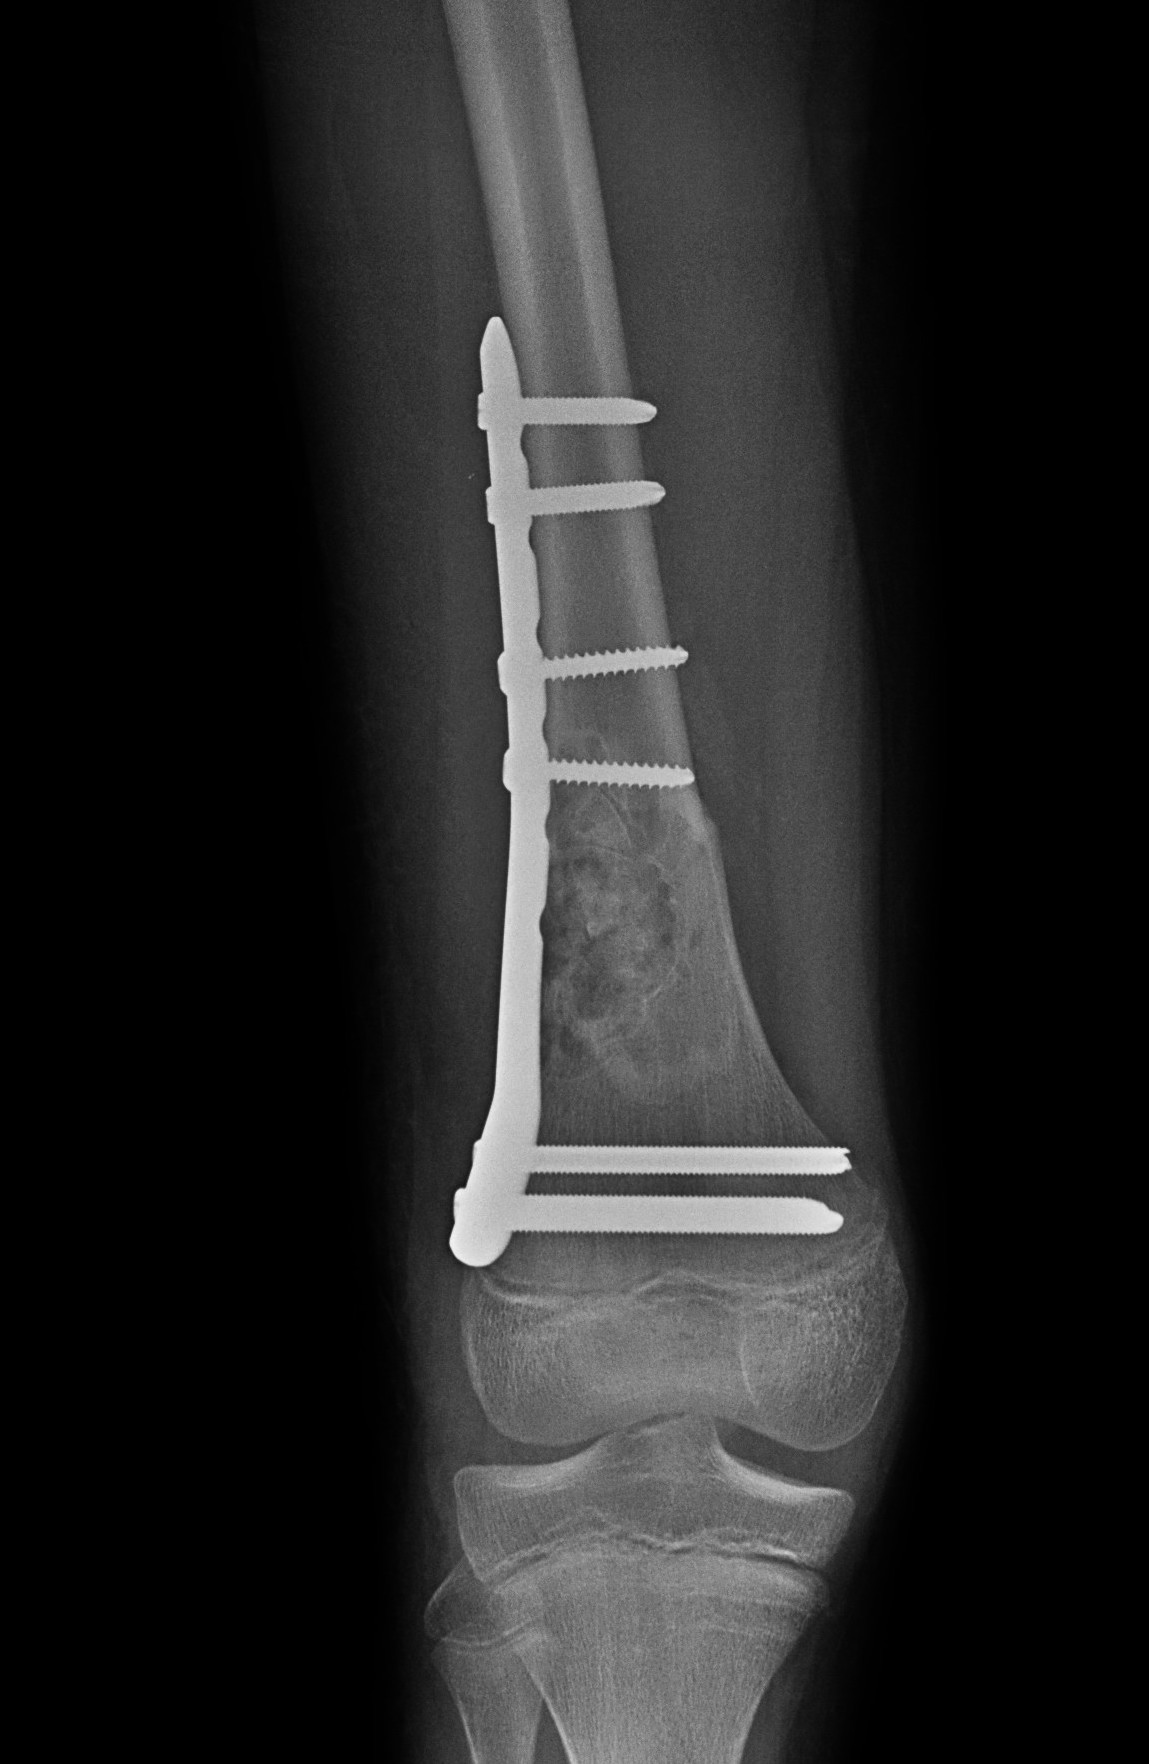

Salter Harris Type II with large Thurston Holland fragement

Technique

AO foundation screw fixation Salter Harris Type II

Reduction

- attempt closed

- may be periosteum blocked on tension / medial side

Medial subvastus approach to knee

- identify Thurston-Holland fragment

- physeal sparing metaphyseal screws

Distal Femur SH2 ORIFDistal Femur SH2 ORIFDistal Femur SH2 Lateral